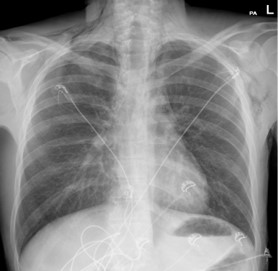

A chest X-ray performed (Figure 1) in the Emergency Department demonstrated significant subcutaneous emphysema. Subsequent computed tomography of the thorax showed extensive pneumomediastinum with a locule of intramural gas possibly reflecting a focal rupture point (Figure 2).

Figure 1: Chest X-Ray.